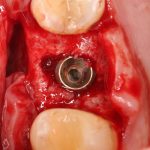

Установка имплантатов.

Напомню, что для этой работы я выбрал субкрестальные имплантаты Ankylos C/X. Они прекрасно сочетаются с любым методом остеопластики.

Я не планирую установку супраструктур или коронок, поэтому на уровень первичной стабильности можно положить болт. Даже наоборот — чем меньше крутящий момент при установке, тем лучше. Для имплантатов Ankylos и подобных им, это особенно важно. В общем, момент силы при установке — не более 10-15 Нсм.

Ремарка: имплантаты с предустановленными имплантодержателями хороши тем, что с ними легко контролировать позиционирование имплантатов. В случае с Ankylos С/Х - еще и крутящий момент. Имплантодержатель должен отсоединяться от имплантата с легким щелчком. Если его клинит, и тебе приходится прикладывать для этого усилия, то ты, однозначно, превысил момент силы во время установки имплантата. Следовательно, жди проблем.

Глянем на то, что получилось: